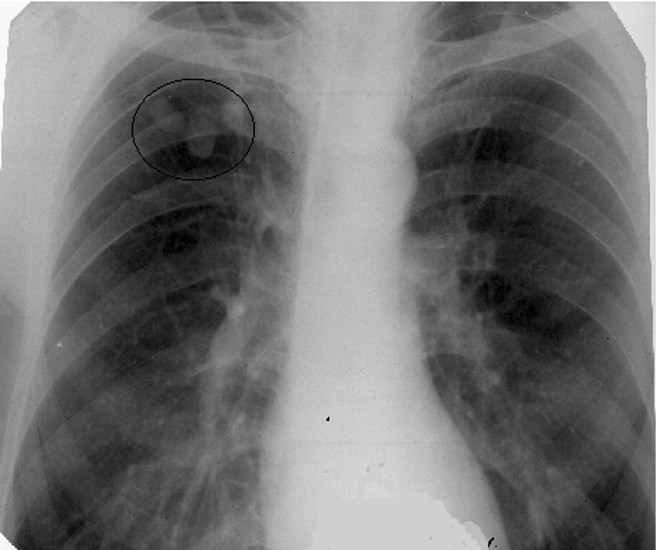

- физикальное обследование больного: патологические изменения в легких могут не обнаруживаться, хрипы прослушиваются только при распространенных инфильтративных изменениях в легочной ткани вокруг туберкулемы;

Кроме того, для диагностики туберкулемы проводят бронхологическое обследование с катетеризационной биопсией, пункцией бифуркационных лимфатических узлов. Данные методики позволяют поставить правильный диагноз в 90% случаев.